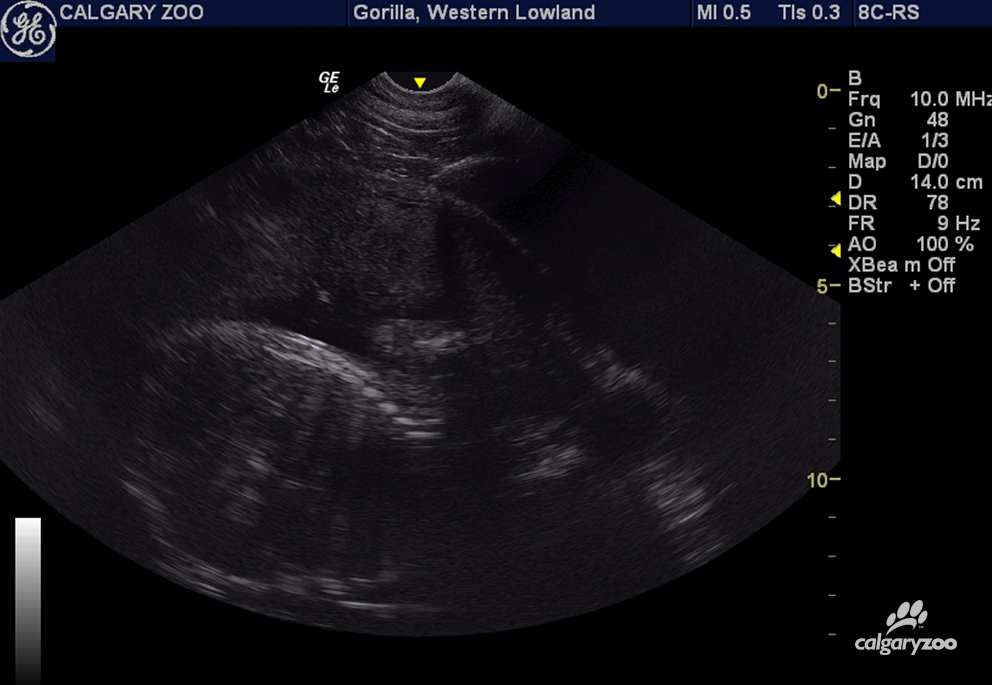

There are regular ultrasounds. There are behavioural checks. And, Kioja has been introduced to a doll-baby to get her used to the idea of being a mother.